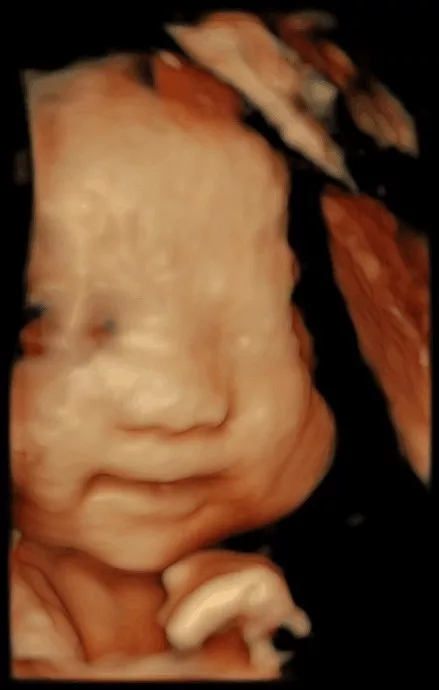

“妈妈,虽然我还在您的肚子里没有和你见面,但是我能感受到您每天的喜怒哀乐。

我喜欢您开森的时候,与我一起分享您的喜悦;我喜欢您享受到美味时,那幸福的味道;当然,我更喜欢您和爸爸一起为我读故事与交谈;当您不高兴、生气的时候,这会让我觉得不安,宝宝希望您永远笑对生活,让不开森的事情成为浮云飘散”